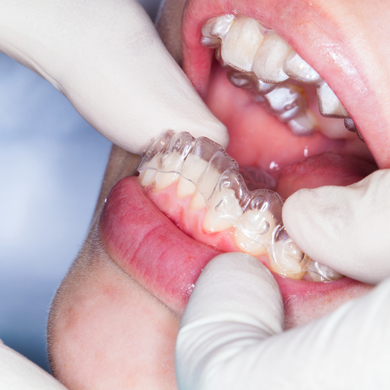

ارتودنسی شفاف یا نامرئی

الاینرهای ارتودنسی شفاف جایگزین محبوبی برای ارتودنسی ثابت هستند. این سیستم‌ به جای استفاده از براکت‌ها و سیم‌ها برای صاف کردن دندان‌هایتان، از یک سری پلاک های شفاف و سفارشی استفاده می‌کند. هر الاینر به مدت یک تا دو هفته استفاده میشود، سپس با شماره بعدی تعویض میگردد. با گذشت زمان، الاینرهای شفاف دندان های شما را به موقعیت مناسب خود حرکت می دهند. به دلیل متحرک بدون در غذا خوردن تداخلی ایجاد نمی کند و ازنظر مکانیکی مانند ارتودنسی ثابت عمل می کند. البته همه بیماران کاندید درمان با ارتودنسی شفاف نیستند.